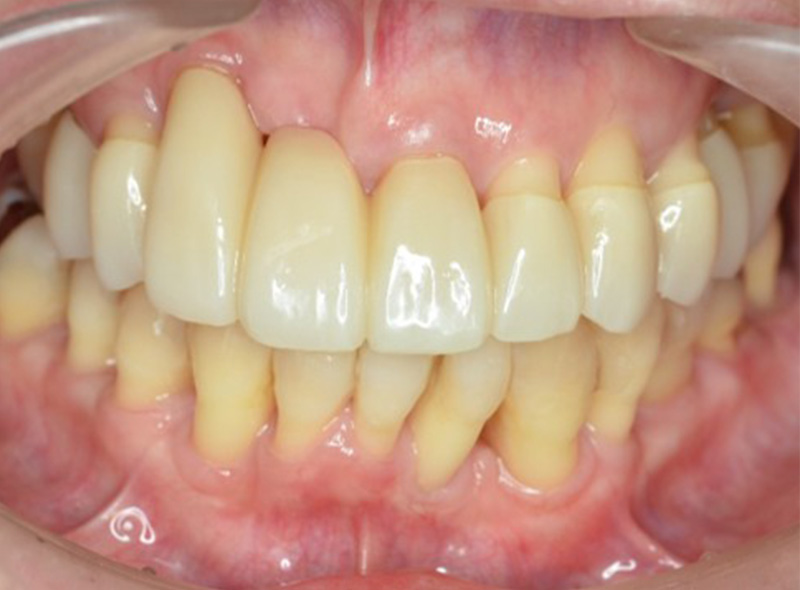

歯周再生療法 歯周矯正治療 ジルコニアセラミック治療

Before

After

| 主訴 | 歯がぐらぐらする。歯周病を治したい。 |

|---|---|

| 治療期間・回数 | 約2年・約15回 |

| 費用 | 2,300,000円 |

| デメリット・注意点 | 詰め物・被せ物の調整が難しく、割れた場合は再治療が必要。 |